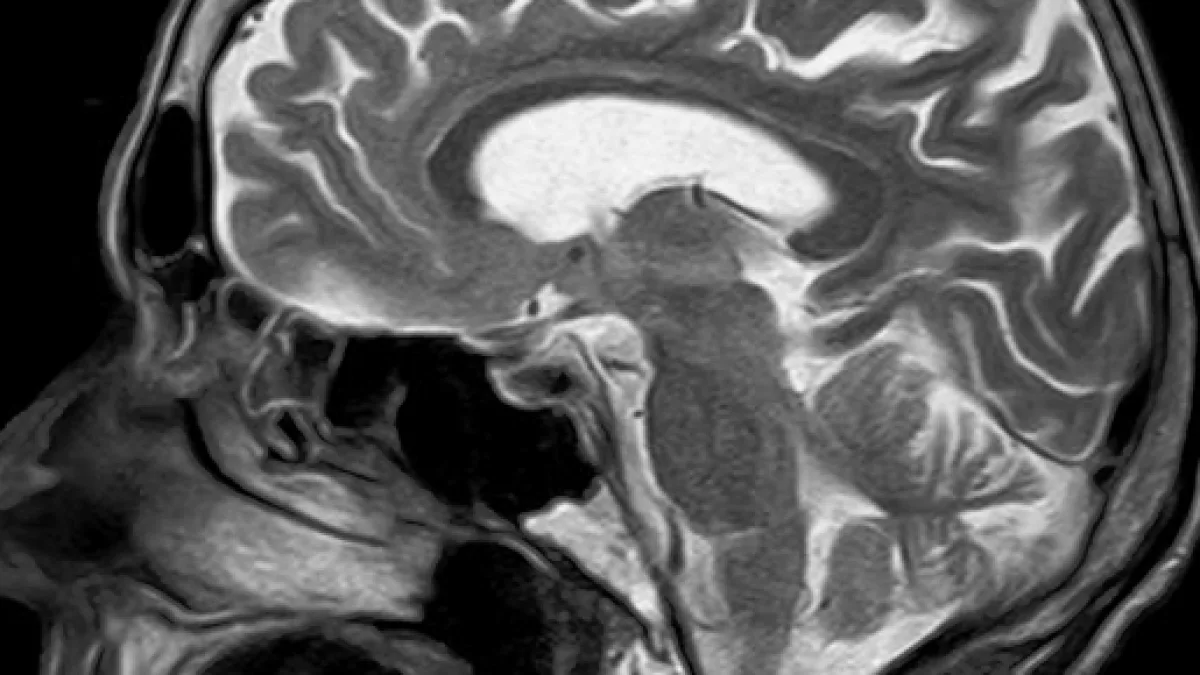

Magnetic resonance imaging (MRI) scans are painless, but for the patient waiting for the scan to reveal potential health issues, the emotional strain can be simply terrible. Many patients discuss their fears on Twitter.